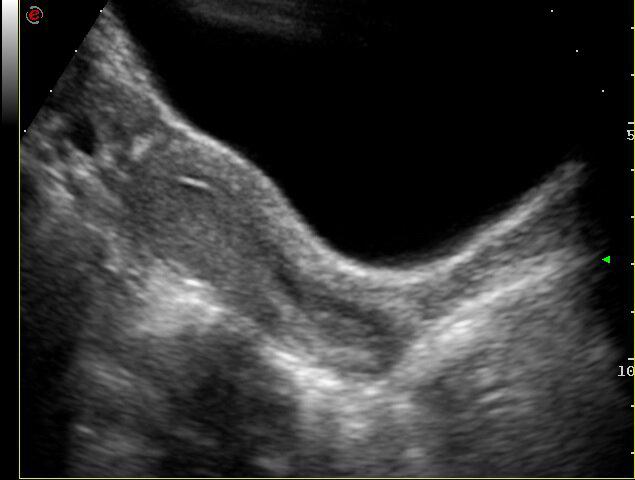

Los avances en este capítulo son extraordinarios. Bien empleados, puede decirse que muy pocas mujeres quedan sin diagnóstico en el caso de presentar patologías. La antigua "laparotomía exploradora" como método para establecer la causa de una enfermedad ginecológica, ha desaparecido en la actualidad. Ya no se concibe operar sin diagnóstico previo. Los avances continuos en el campo de las imágenes, nos permite conocer con creciente precisión, la condición de los órganos genitales pelvianos femeninos. La ecografía es el primer gran auxiliar, indispensable casi, para evaluar el estado anátomofuncional de útero y ovarios por vía abdominal transvesical en mujeres delgadas y sin relaciones sexuales o por vía transvaginal, en aquellas con actividad sexual que aceptan esta vía o en obesas, donde el espesor de la pared abdominal dificulta una buena visualización. En las figuras 1, 2, 3 4, 5 observamos ejemplos de genitales normales y de alguna patología. Hoy día la técnica denominada 4D brinda imágenes excelentes por lo que es empleada con frecuencia en el estudio morfológico del feto en su tercer trimestre.